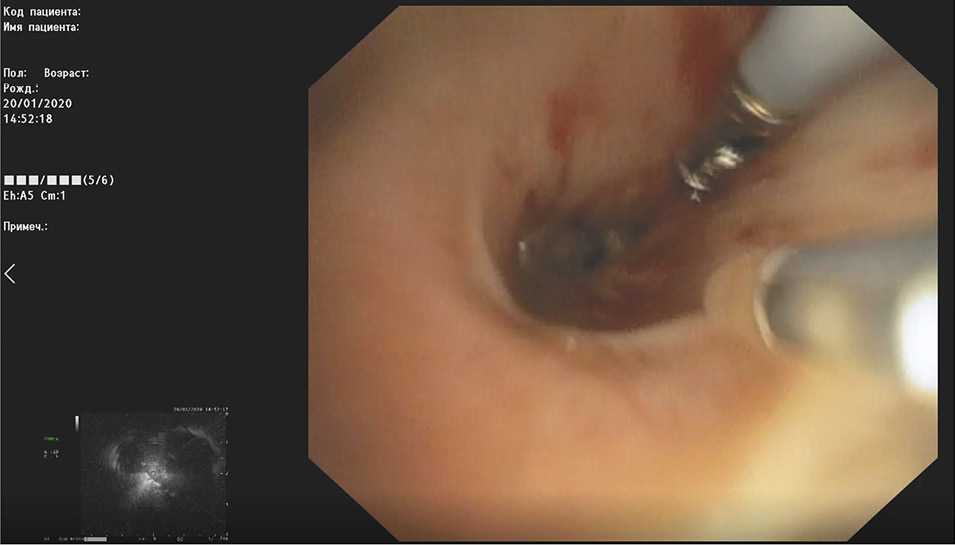

В случае сонографического выявления опухоли по тубусу-проводнику, установленному на дистальном колпачке, в проекцию данного новообразования проводятся биопсийные щипцы (рис. 4).

Рис. 4. Проведение биопсийных щипцов в проекцию новообразования.